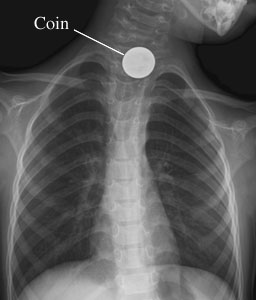

Chest X-Ray of a Swallowed Object